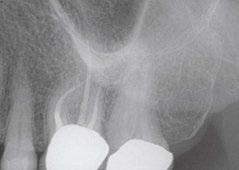

Additionally, with IRR, the outline of the root canal is usually distorted and appears contiguous with the resorptive defect, while with external resorption, the root canal outline appears normal and can usually be seen running through the radiolucent resorptive defect, as there remains a thin layer of dentin separating the canal from the resorptive area9-10 (Figures 2A-2D).

The radiographic appearance of IRR is a fairly uniform radiolucent enlargement of the root canal. There would only be alveolar bone loss adjacent to the resorption if the resorption perforates into the PDL. The best and most accurate tool we have for diagnosing IRR and determining the path of the perforating

lesion is cone beam computed tomography (CBCT). It is best to use a limited field of view (FOV), as opposed to the larger FOV used with other disciplines in dentistry. A smaller FOV increases image resolution, while at the same time providing a lower effective radiation dose to the patient. It is worth noting that in Case 2, one cannot visualize the resorptive defect from just looking at the periapical radiograph. It has been shown in countless studies that CBCT gives a more accurate diagnosis and better visualization of periapical pathology.11-13

Figures 2A-2D: 2A: Periapical radiograph of tooth No. 21. Large resorptive defect is noted in external cervical region. Blue arrows point to a thin layer of predentin that appears to be running through defect. Outline is what remains of root canal wall. Tooth tested vital, and diagnosis of invasive cervical root resorption was made. Due to minimal remaining tooth structure, extraction was advised. 2B-2D: Sagittal, coronal, axial slices show resorptive defect external to root canal